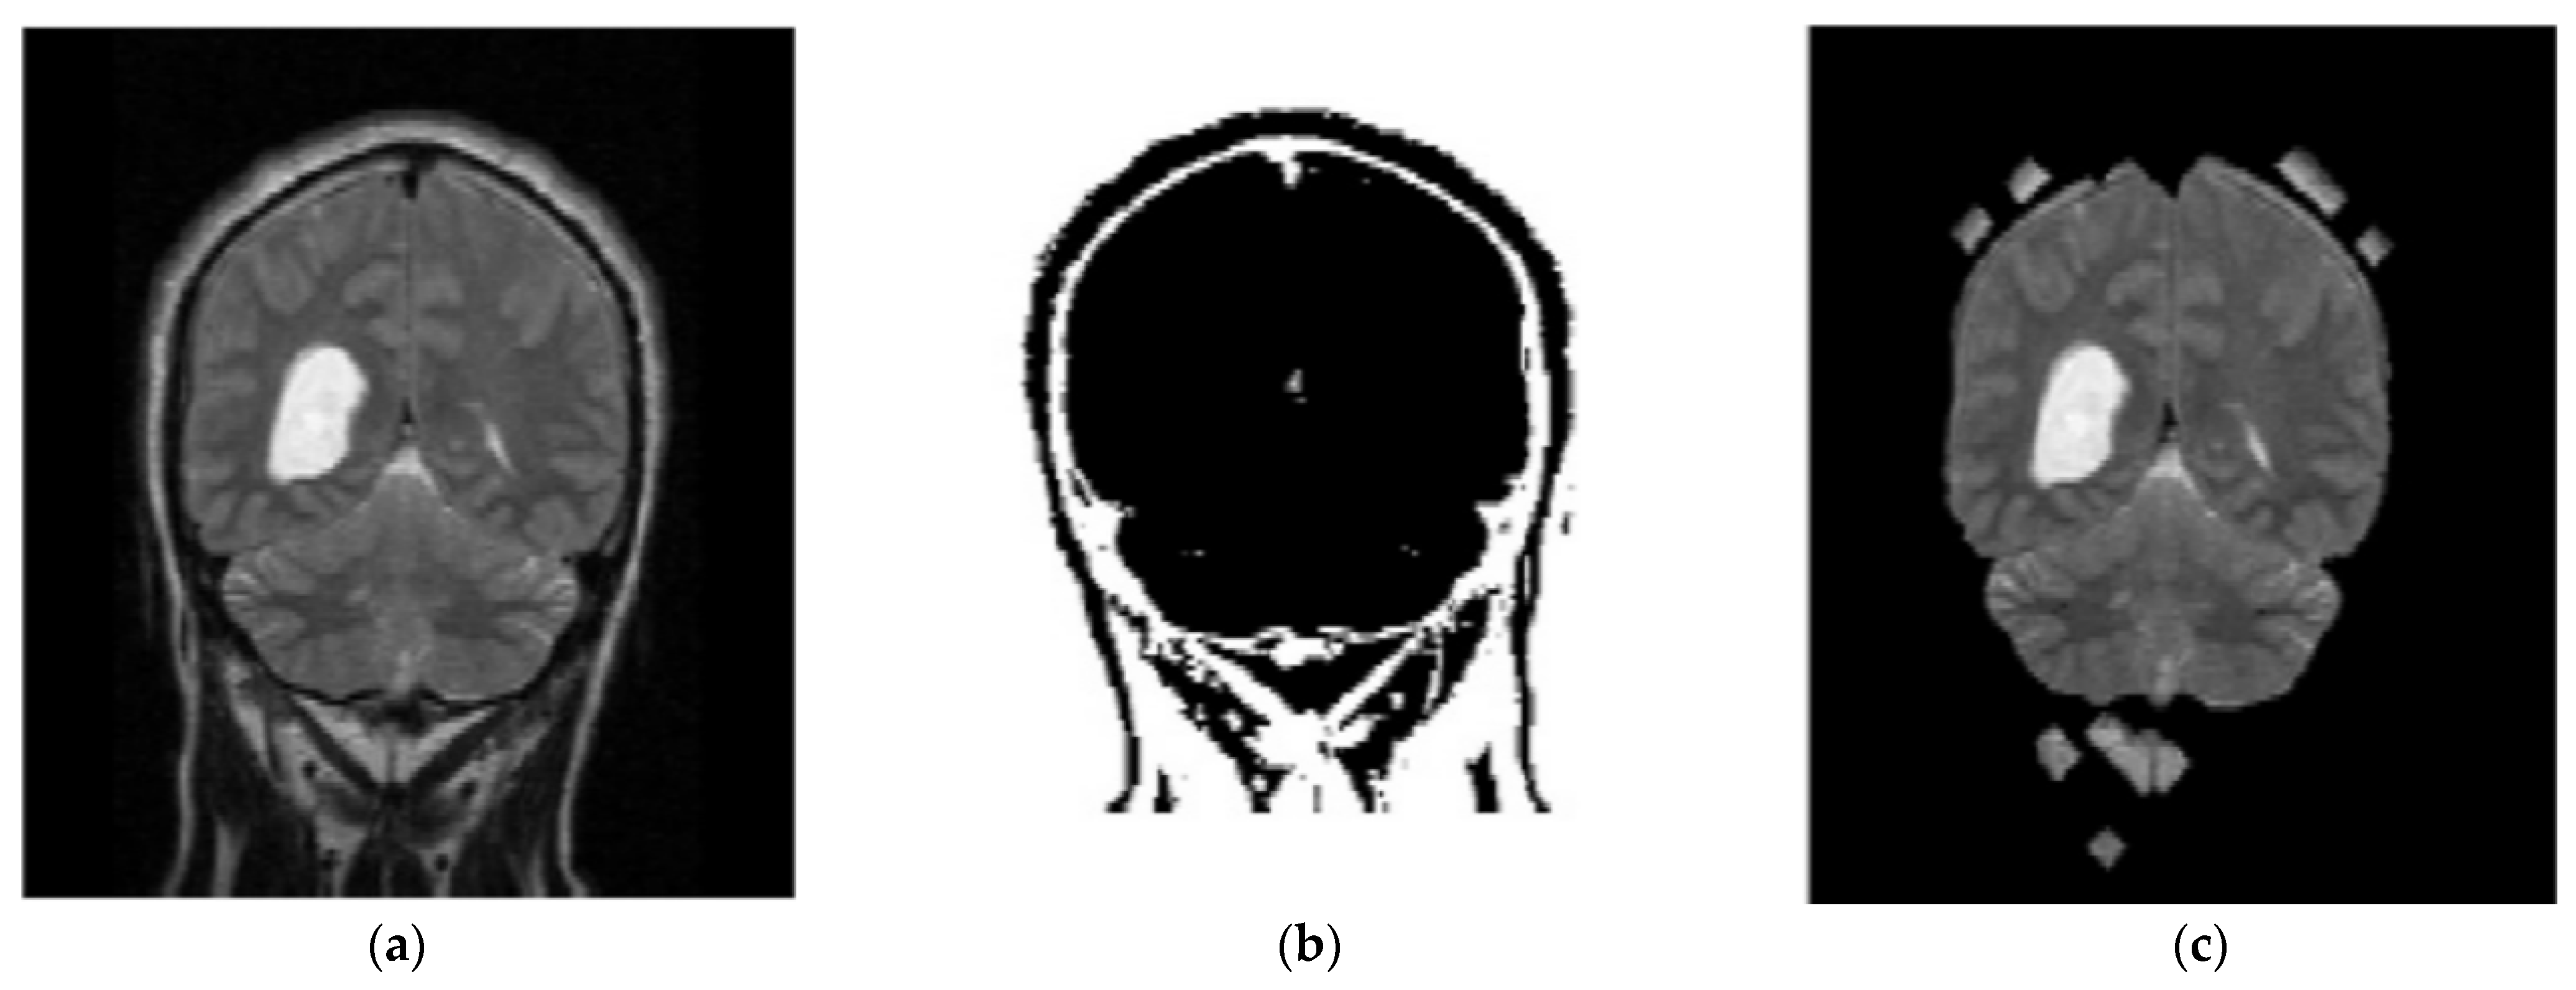

3.2. Stage 2: Segmentation—Enhanced Fuzzy C-Means Clustering